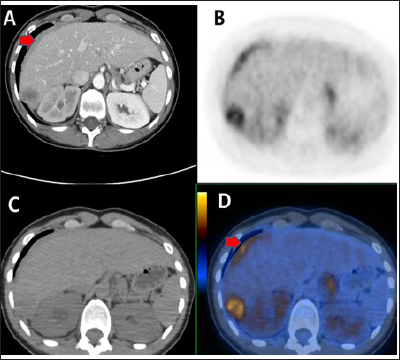

Figure 2: Abdominal pelvic CT with contrast enhancement(A) showed 3.2 x 2.0cm sized central low peripheral enhancing hepatic mass in Rt. liver tip portion and soft tissue lesion with enhancement in the perihepatic space. Liner FDG uptakes along the perihepatic space and focal FDG uptake in the right livers suggesting peritoneal carcinomatoses and hepatic metastasis demonstrated on the F-18 FDG PET-CT (B, C, D).